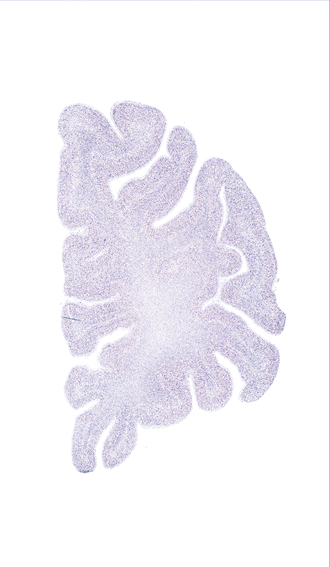

Microscopy

Slice ID: r1-0175

Plate NR: 04-05

Position: -38,2 mm